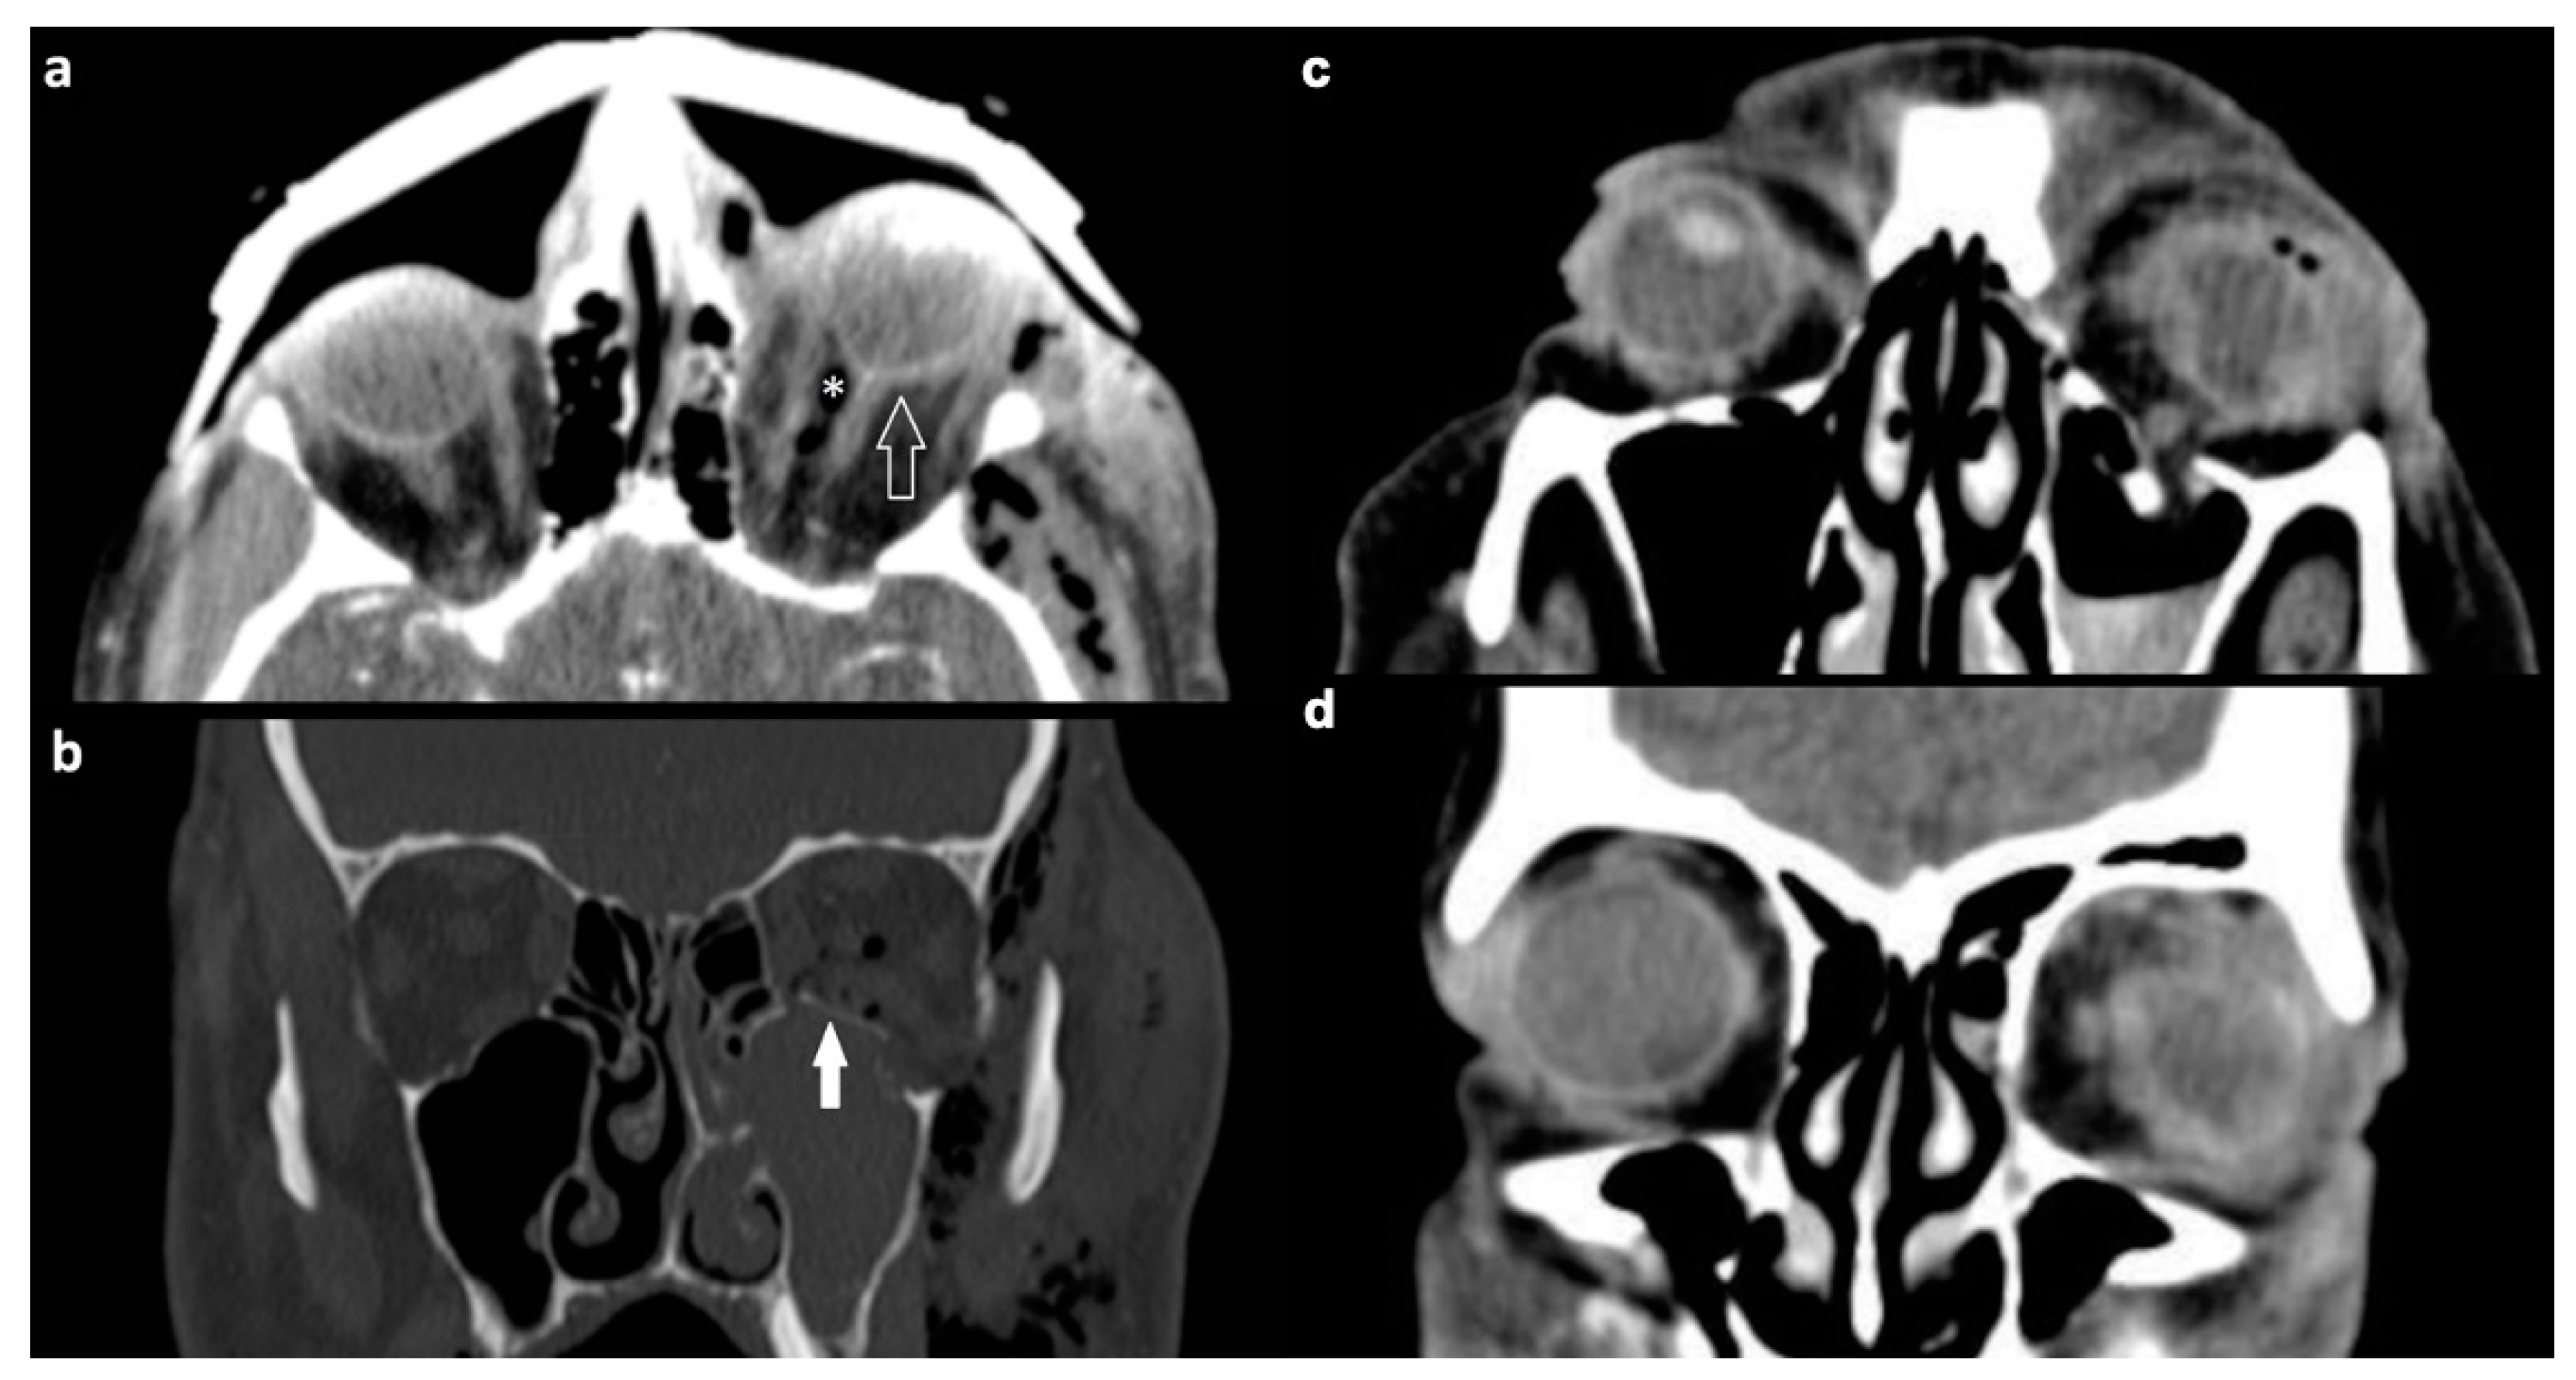

3.2.1. Osseous Injuries

| Type of Fracture | Right Orbit n (%) | Left Orbit n (%) | Total n (%) |

|---|---|---|---|

| single wall | 51 (58.0) | 40 (49.4) | 91 (36.8) |

| two walls | 21 (23.9) | 22 (27.2) | 43 (17.4) |

| three walls | 13 (14.8) | 12 (14.8) | 25 (10.1) |

| four walls | 2 (2.2) | 6 (7.4) | 8 (3.2) |

| four walls and orbital apex | 1 (1.1) | 1 (1.2) | 2 (0.8) |

| bilateral fractures | 78 (31.6) | ||

| total | 88 (35.6) | 81 (32.8) | 247 (100) |